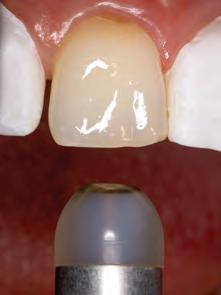

A 31-year-old woman presented with cosmetic concerns regarding her smile and requested a conservative enhancement. After clinical and radiographic analysis, digital 35mm photographs were taken and reviewed by the restorative clinician, technician, and surgeon (Fig 1). A digital impression was taken of the maxillary and mandibular arches using an intraoral scanner (Trios 3, 3Shape; Fig 2), and a smile design was developed with NemoSmile Design 3D software (Nemotec; Fig 3a). This allows for a facially driven smile frame to be created using reference lines of facial and smile proportions and natural teeth shapes and textures from the digital library (Fig 3b).

After developing the simulated mock-up, a 3D-printed resin model was created using CAD software (Fig 4a), and a clear PVS matrix (Exaclear, GC America) was fabricated to replicate the printed diagnostic wax-up using a nonperforated tray (Fig

4b). This matrix was used to create an intraoral motivational mock-up with bis-acryl composite (Luxatemp Ultra, DMG). This additive mock-up provides the interdisciplinary team with an intraoral translation for evaluation (Fig 5). Upon evaluation of the digital smile frame and the clinical translation, it was determined that multiple esthetic and restorative requirements were necessary for an optimal biologic framework, and the interdisciplinary team determined the best sequence for these procedures. The patient was presented with the interdisciplinary treatment possibilities that included restoring the maxillary anterior teeth and premolars with a minimally

invasive preparationless procedure or with less conservative veneer preparations. The restorative materials discussed included injectable resin composites and ceramic (ie, feldspathic, pressable, machinable). For an optimal biologic framework and health, it was determined that connective tissue grafting would be necessary for treatment of the recessiontype defects on the maxillary left central and lateral incisors, canine, and premolars. The patient opted for the conservative preparationless composite veneers using the injectable resin technique followed by a connective tissue surgical procedure using the tunneling technique.